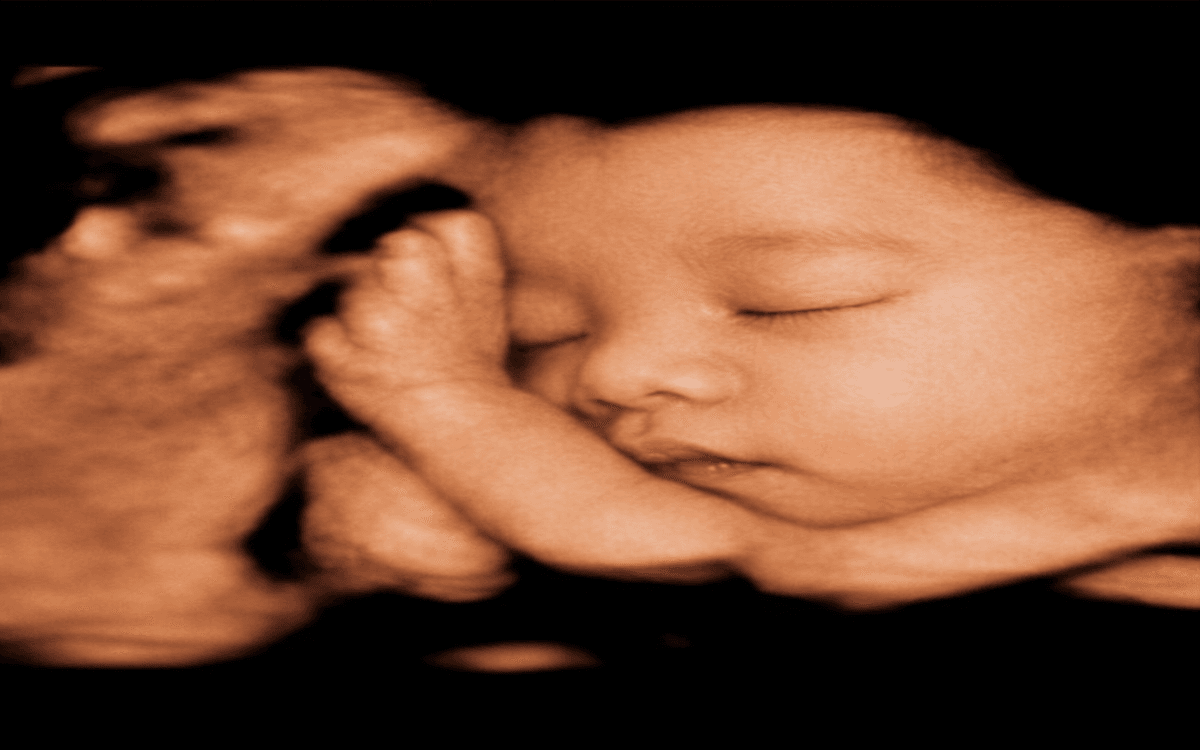

Vuốt để xem sự khác biệt giữa ảnh siêu âm gốc và hình ảnh AI làm nét

Công nghệ AI của LovelyBaby phân tích cấu trúc xương, làm rõ nét từng đường nét chân thực nhất trên khuôn mặt bé để tạo nên bức ảnh kỷ niệm tuyệt đẹp theo bạn suốt đời.